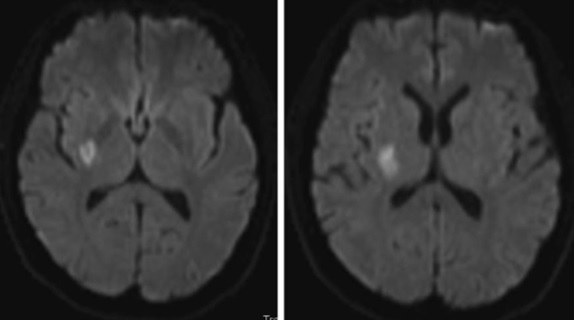

Se trata de un paciente de 51 años, con antecedentes de hipertensión arterial y diabetes. Tuvo una pérdida súbita de la fuerza en el lado izquierdo del cuerpo (miembro superior e inferior) asociado a pérdida del campo visual izquierdo. Al examen físico se confirmaron estos hallazgos. El déficit visual consistía en una hemianopsia homónima izquierda. La imagen muestra:

En esta secuencia de difusión de una resonancia magnética se aprecia una lesión isquémica (área blanca) en la cápsula interna derecha, en la parte más posterior del brazo posterior. Por esta razón el paciente no tiene comprometida la cara.

Interpretación: Un compromiso por clínica del tracto óptico derecho (hemianopsia homónima derecha) asociado a un déficit motor de origen capsular (miembro inferior y superior), nos indica que ha un compromiso del territorio de la arteria coroidea anterior. Esta arteria es rama directa de la arteria carótida interna, en su segmento comunicante. Emerge después de la arteria comunicante posterior y se dirige hacia atrás por la cisterna ambiens. Tiene dos segmentos, uno cisternal y otro plexal. El primero da las ramas críticas a la cápsula interna, tracto óptico (bajo el cual discurre), y algo del temporal. El segundo se introduce en el ventrículo lateral y ayuda a formar el plexo coroideo del ventrículo.